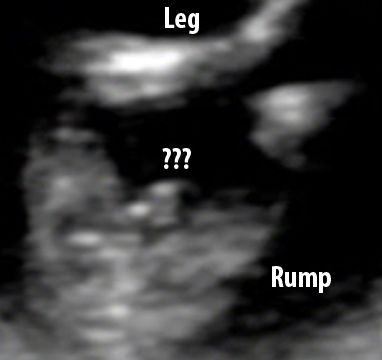

DH and I had a laugh when the rump shot yielded an interesting angle on the gender!

Maybe it's the umbilical chord... or maybe it's something else?

What do you lovely ladies think?

Do you think the stork is bringing us a girl? Or a boy?